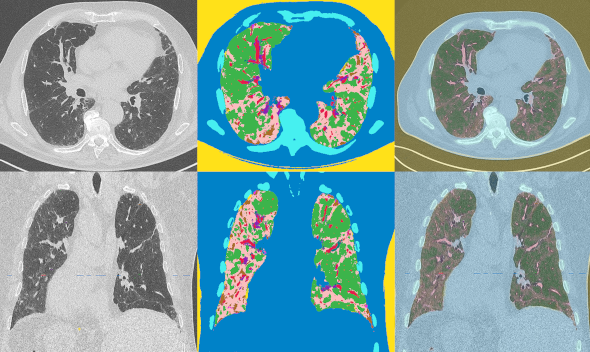

Figure 1. TDM thoracique axiale et coronale, cartes de segmentation et images fusionnées chez un patient de 79 ans ; vert : normal ; rose : verre dépoli ; marron : verre dépoli dense ; rouge : vaisseaux ; violet : condensation ; bleu : tissus mous ; bleu claire : os.